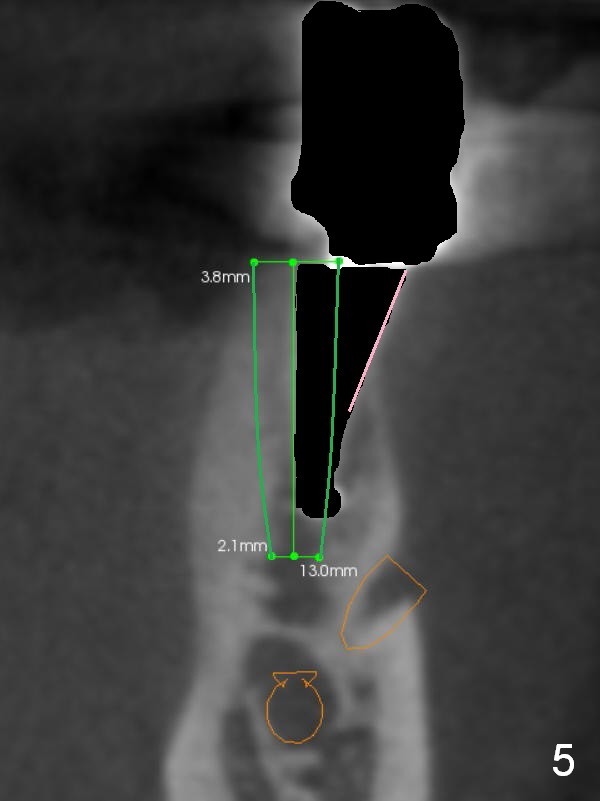

When the osteotomy is intentionally placed as lingual as possible (Fig.3 red area), the implant (Fig.4 green) will end up in a more favorable position with a large buccal gap (*). The latter allows to place collagen membrane (Fig.5 pink) and bone graft (Fig.6 red circles).